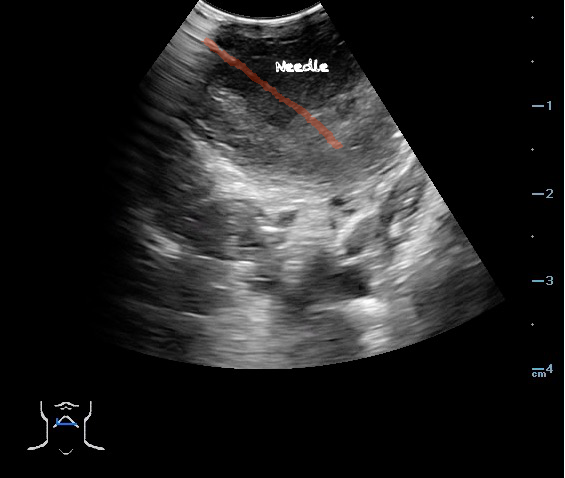

- Ultrasound-guided needle aspiration of a PTA:

- The depth of the abscess cavity from the mucosal surface should be noted to determine the length of the needle required to drain the abscess.

- Figure 45. and 46. PTA aspiration

Video 27. PTA Aspiration - Complete aspiration verified by ultrasound:

- Figure 49 and 50. PTA Aspiration Resolution

- The ability to simultaneously image and introduce the needle allows the emergency physician to track the entire course of needle and prevent complications such as puncturing the carotid artery.30-32

- Use Color Doppler to determine the relationship of the carotid artery to the abscess cavity prior to performing aspiration.